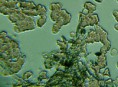

Mnohé štúdie dokazujú pozitívny efekt Bioquantu - jeho laserového žiarenia na postupnú elimináciu baktérií, vírusov či lariev parazitov migrujúcich v krvnom riečišti. Ide najmä o normalizáciu imunity, špecifickej i nešpecifickej. Navyše termodynamický efekt laseru pri ožarovaní krvi, ktorý síce náš organizmus nevníma a ľudské bunky neohrozuje, spôsobuje zvyšovanie termodynamickej teploty najmenších štruktúr - teda mikroorganizmov. Tieto následne ničí aktivovaná imunita a zvýšená baktericídna aktivita krvného séra. Sú zaznamenané pozitívne efekty pri vírusoch HIV/AIDS, vírusoch encefalitídy, pri borelióze, pri prevencii chrípky. O účinkoch na baktérie svedčí aj vysoká účinnosť pri výskytu akné baktérií. Prostredníctvom aktivácie porfírinov sa uvoľňujú voľné radikály a tým zabíjajú baktérie zvnútra..

Laserové ožarovanie krvi navodzuje i úpravu pomerov populácie T helperov a T supresorov smerom k normalizácii a úprave celkového počtu T lymfocytov a vyvoláva zmenu aktivity enzýmov imunokompetentných buniek. To je dôležité pre celom rade ďalších ochorení.